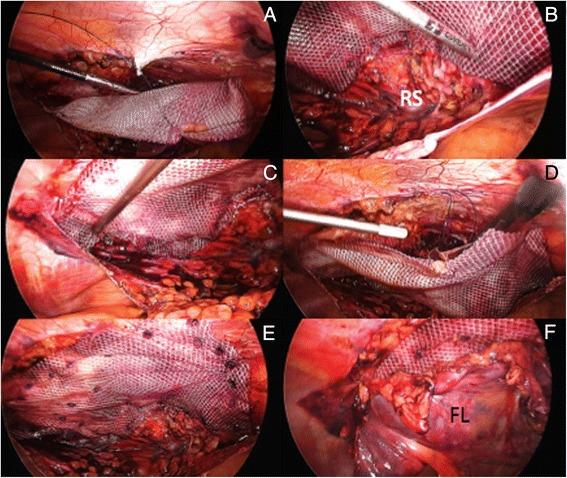

Correspondence: Laparoscopic repair of abdominal wall hernia--"How I do it"--synopsis of a seemingly straightforward technique.

Abdominal wall hernia repairs are commonly performed worldwide in general surgery. There is still no agreed consensus on the optimal surgical approach. Since the turn of the twenty-first century, minimally invasive techniques have gained in popularity as they combine the advantages of limited abdominal wall dissection, reduced post-operative pain and risk of complications, and shorter hospital stay. Although the added cost incurred by using sophisticated laparoscopic instruments may be quite substantial, it is precisely counterbalanced by an improved morbidity rate, faster discharge home and time to return to work. Laparoscopic abdominal wall hernia repair is often challenging, as it requires good anatomical knowledge, eye-hand coordination and diversified laparoscopic skills. The objective of this article is not to present another set of personal data and to compare it with already published results on this matter, but simply to offer comprehensive guidelines on the practical aspects of this relatively new technique. Some of these steps have already been discussed but most of the time in a scattered way in the surgical literature, while others are the fruit of a personal expertise grasped over the years.